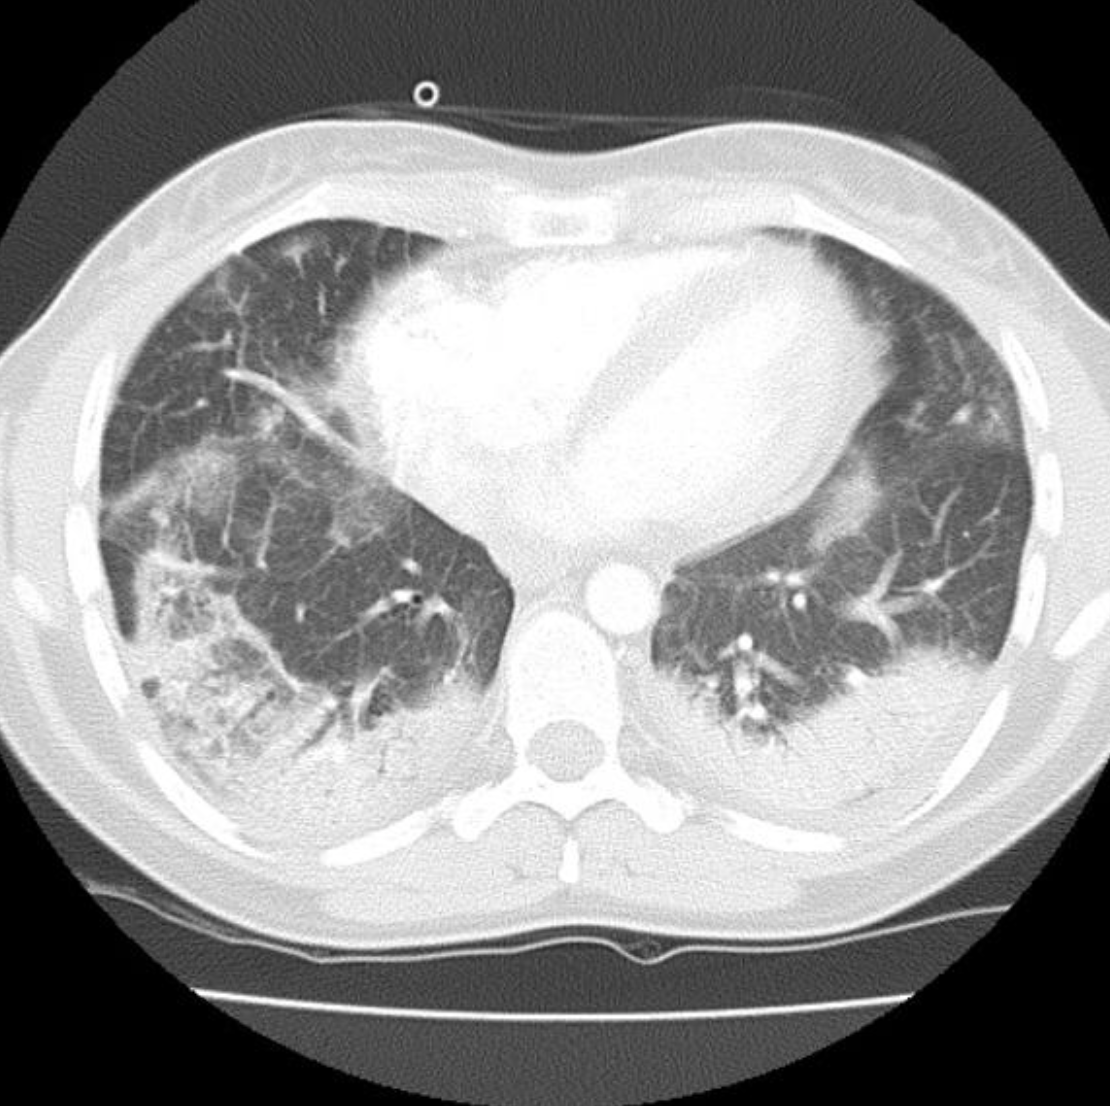

Cryptogenic Organising Pneumonia

• ALSO KNOWN AS

• bronchiolits obliterans organising pneumonia (BOOP)

• HRCT findings

• Patchy consolidation/GGO

• Subpleural, peribronchial

• Lower lung > upper

• +/- centrilobular nodules

• +/- large irregularly shaped masses

• ATTOL sign (1st picture) crescent shaped opacity

• REVERSE HALO sign (second picture)

• central GGO with surrouding consolidation.